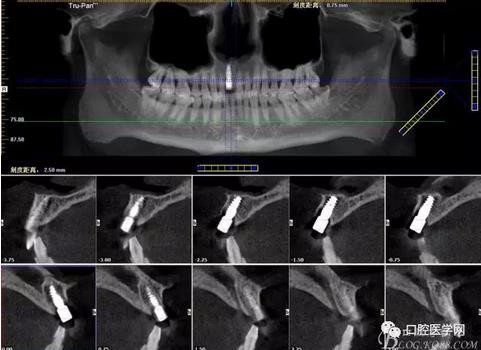

圖3 術(shù)后CT